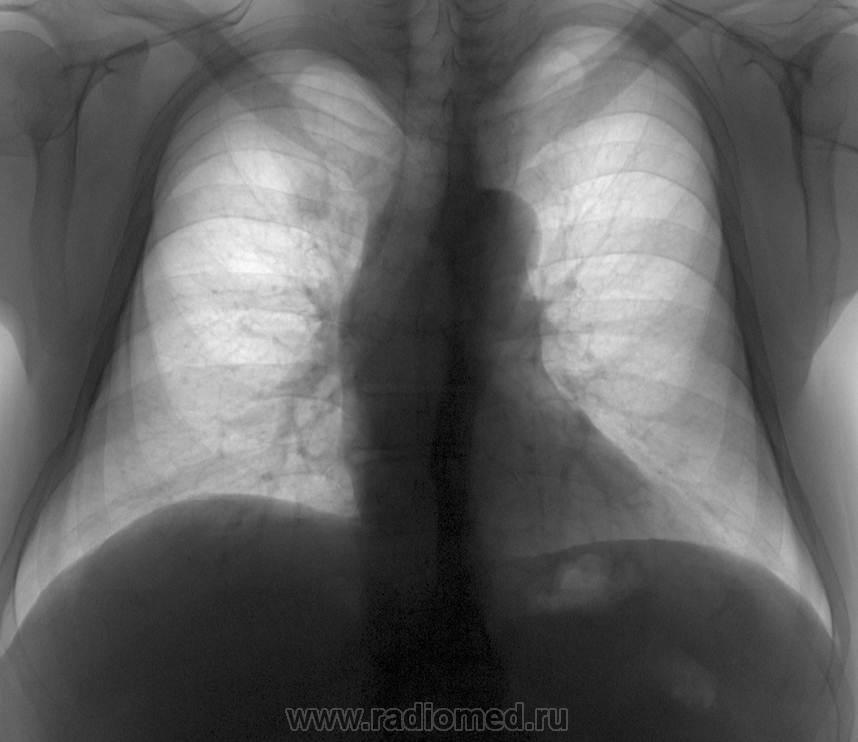

Само по себе обызествление 1-го реберного хряща встречается конечно часто, каждый день и помногу...но ведь здесь - остеома....или я не прав?

, которая видна на боковой рентгенограмме...

Вы абсолютно правы, в боковой (и задне-наклонной)...даже как бы двойной контур, причем второй менее интенсивный и нечеткий, так что может, что и остеохондрома.

Скорее всего все-таки обызвествление/остеофиты, коллеги. Они могут быть очень массивными, часто видны на КТ.

Может что Вы и правы, просто смущает односторонность, размеры, контуры и направление роста, что в целом выходит за рамки просто обызествления. Хотя, должен согласиться, форма и размеры могут быть вариабельными.

Случай представлен больше в дифференциальном плане, учитывая схожесть в прямой проекции и одностороность.